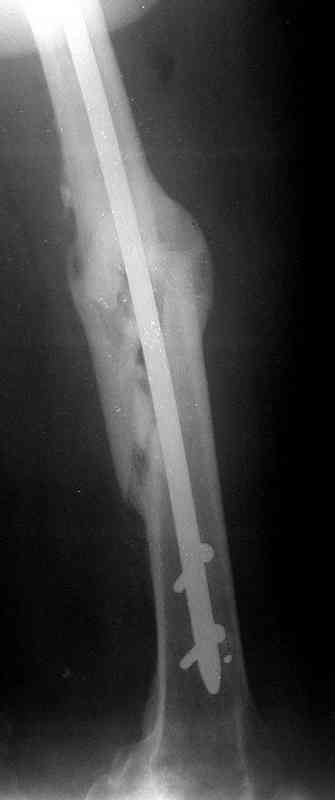

Уважаемые коллеги!На прилагаемых снимках - состояние после оперативного вмешательства (открытый перелом левого бедра в средней трети):

МОС, стержень нефиксированный. С момента операции прошло 8 месКак по Вашему мнению происходит консолидация? Допустимо ли смещение или необходима повторная операция по выравниванию конечности? Если да, какой метод рекомендуете (фиксированный стержень, пластина)?Буду благодарен за оперативный ответ.

Вы не пишете, есть ли сейчас болезненные проявления, и какие. Как пациент ходит. Какова функция колена. Ось выглядит приемлемо. Рентгенологически на сращение непохоже. Если есть клиника несращения (боль, хромота), то лучший выбор - закрыто рассверлить и перештифтовать блокированным гвоздем. Желательно определиться поточнее, нет ли проблемы с длиной , чтобы попутно и ее решить. И не создать. Ну и прежде всего исключить инфекцию. Если это инфицицированное несращение, план надо другой.

При таком диаметре штифта не удивительно, что перелом не сросся (кстати, какой диаметр и что за модификация штифта?).

Допустимо ли смещение...

В этой проекции угловое смещение градусов 15-20 - многовато будет. Есть ли укорочение?